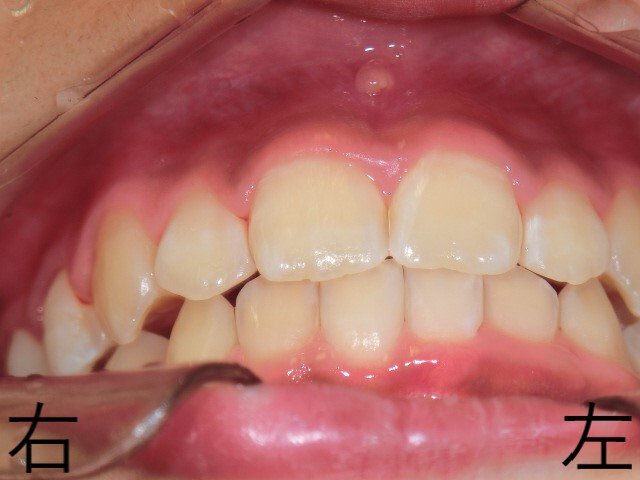

12歳時点で、右左ともに上下臼歯の噛み合わせが安定し、良好な咬合が確認されました。